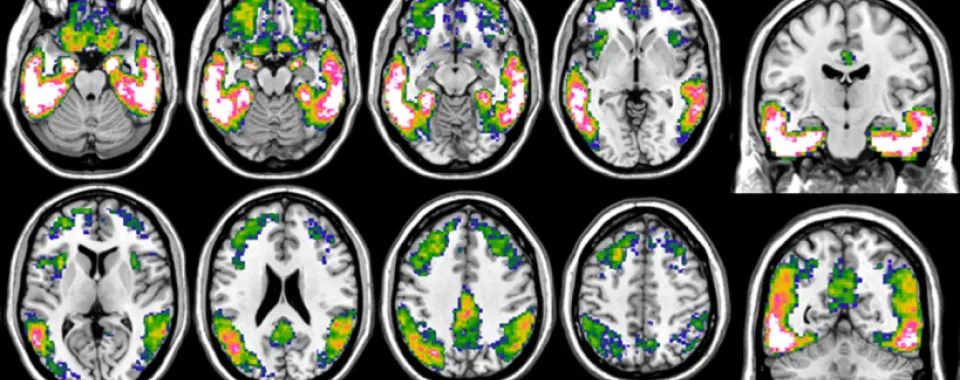

Imagerie de cerveaux de patient-es atteint-es de la maladie d'Alzheimer

Le Flortaucipir est un radiotraceur se liant à la protéine tau mis au point par une compagnie pharmaceutique et approuvé en 2020 par la Food and Drug Administration (FDA). Il permet d’observer son accumulation dans le cerveau, et surtout sa distribution, et d’évaluer précisément son rôle dans la manifestation clinique de la maladie.

«Cette avancée est déterminante pour mieux prendre en charge la maladie d’Alzheimer. Récemment, des médicaments ciblant l’amyloïde ont démontré des résultats positifs. De nouveaux traitements ciblant la protéine tau semblent aussi prometteurs. En parvenant à détecter la maladie le plus tôt possible, avant que le cerveau ne soit trop endommagé, et grâce aux nouveaux traitements, nous espérons réellement pouvoir faire une différence dans le futur et pour la qualité de vie des malades», souligne Valentina Garibotto. «De même, nous commençons à cartographier la distribution de tau afin de comprendre comment sa localisation sur les différentes régions du cerveau influe sur les symptômes.» En effet, les causes et les différentes étapes de la maladie s’avèrent beaucoup moins uniformes qu’on ne le pensait et la susceptibilité individuelle aux mêmes phénomènes doit être mieux comprise.